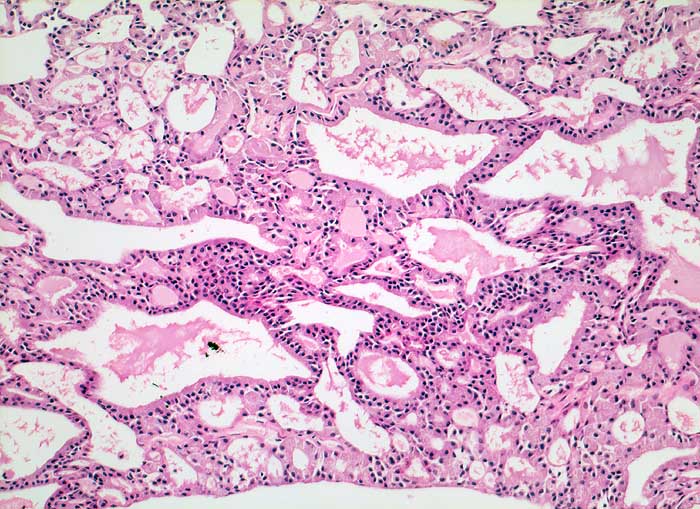

p/ Azinuszellkarzinom der Glandula Parotis

Azinuszellkarzinom der Glandula Parotis

Die zytologische Diagnose des Azinuszellkarzinoms basiert auf dem Nachweis von Azinuszellen bei gleichzeitigem Fehlen von Gangstrukturen. Die Tumorzellen gleichen normalen serösen Azinuszellen. Zytoplasma ist reichlich vorhanden und variiert von schaumig bis grobgranulär. Degranulierte Zellen erscheinen schaumig, Zellen mit dichtgepackten Granula gleichen Onkozyten. Die Granula der Onkozyten sind aber feiner. Die Tumorzellkerne sind meist ziemlich wenig atypisch und monomorph. Das Chromatin variiert von fein bis mittelgrob. Intranukleäre Zytoplasmaeinschlüsse kommen vor. Die oft vorhandenen zahlreichen Nacktkerne müssen von ebenfalls oft vorhandenen Lymphozyten abgegrenzt werden. Die meist hoch differenzierten Tumoren können mit normaler Speicheldrüse verwechselt werden.